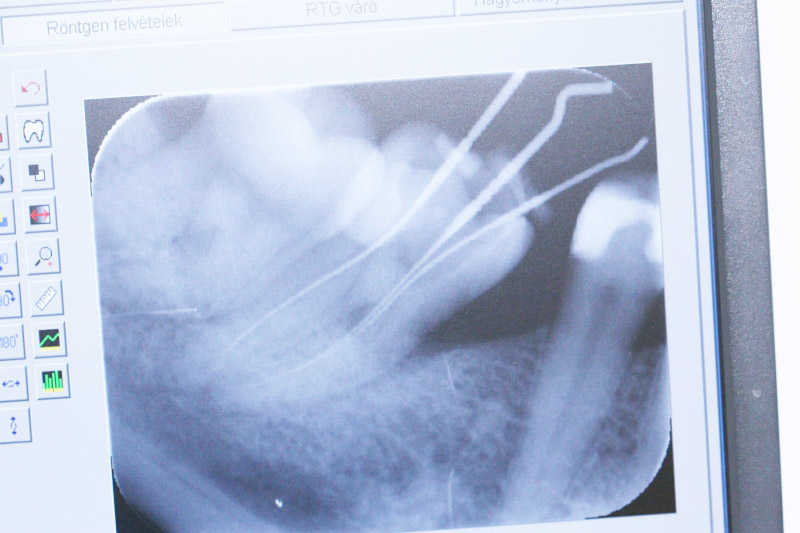

A tűskontroll látható a röntgenképen. A gyökérkezelő tűk segítségével íly módon meghatározható a gyökerek hossza. Várandós kismamáknál ez a lépés nem röntgennel, hanem egy speciális apexlokátorral történik.

A tűskontroll látható a röntgenképen.